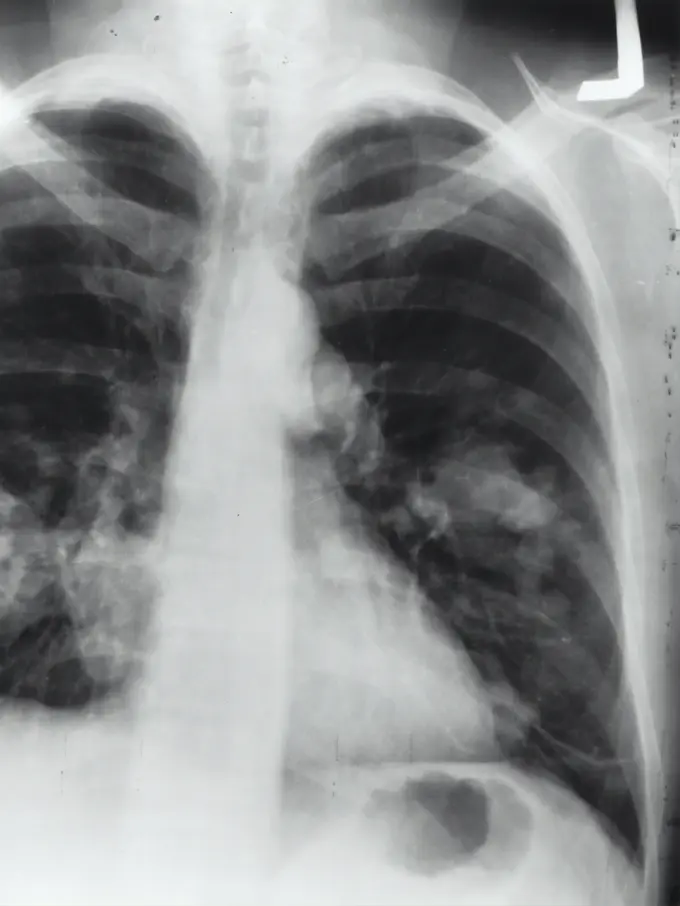

Fimela.com, Jakarta Kanker paru-paru menjadi salah penyakit kelompok kanker yang paling banyak menyebabkan kematian. Hal ini dikarenakan kanker paru-paru umumnya tidak memiliki gejala di awal kemunculan.

Oleh karenanya Spesialis pulmonologi, Prof dr Elisna Syahruddin PhD SpP(K) mengatakan pasein dengan kanker paru-paru biasanya sudah tingkat lanjut jika berkonsultasi dengan dokter. "Biasanya udah kena dari 20 tahun tapi tidak terasa kalau tidak dicek. 80 persen diketahui sudah tingkat lanjut, 20 persen karena insidentil," ujar Prof Elisna dalam acara peluncuran aplikasi Pulih.

Ia juga menyebutkan jika skrining kanker hanya bisa dilakukan saat pasien belum bergejala dan dilakukan atas kehendak sendiri. Perhimpunan Dokter Paru Indonesia (PDPI) merekomendasikan skrining dilakukan oleh mereka yang berusia di atas 45 tahun, perokok pasif/aktif, bebas perokok kurang dari 10 tahun, memiliki riwayat paru, dan bekerja di lingkungan berisiko.

Prof Elisna mengatakan diagnosis dan pengobatan yang tepat waktu merupakan faktor penting untuk menentukan keberhasilan pengobatan kanker paru-paru.

Masyarakat perlu menghindari faktor risiko kanker paru dan mengetahui gejala kanker paru sehingga apabila merasakan beberapa gejala tersebut, perlu segera melakukan konsultasi kepada dokter agar bisa terdiagnosa lebih cepat. Lebih dari itu, pasien yang sudah terdiagnosa, harus mendapatkan terapi sesuai dengan kondisinya karena kanker paru berkembang dengan cepat.